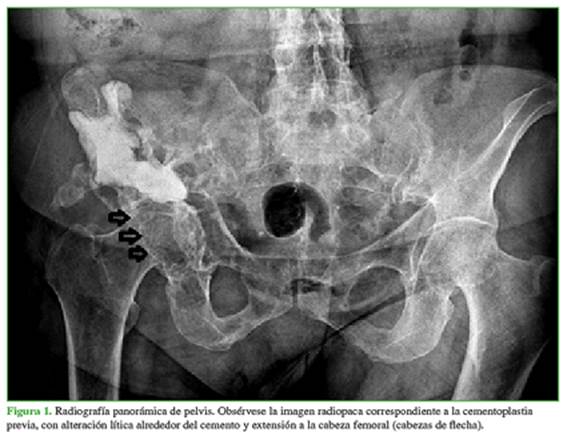

La paciente acudió a nuestra institución en marzo de 2018. En el examen físico, se observó una tumoración palpable en la cara externa del hueso ilíaco derecho asociada a dolor en la cara anterior del muslo homolateral. Refería dolor durante la flexo-extensión de la cadera derecha y a las rotaciones, como así también dolor a la carga sobre ese miembro. Deambulaba únicamente dentro del domicilio asistida con andador. Una radiografía de pelvis (Figura 1) mostró una alteración de la estructura compatible con lesión expansiva que comprometía el hueso ilíaco derecho, de aspecto heterogéneo y bordes irregulares, además de la presencia de cemento producto de la cementoplastia previa.